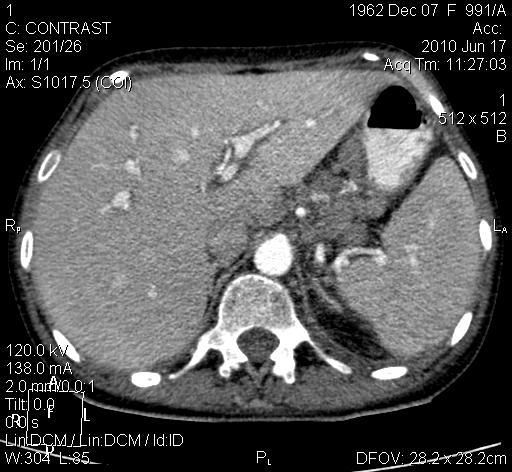

Женщина 47 лет, более месяца боли в эпигастрии, непостоянные, похудела. Около 2 недель боли в позвоночнике. Поступила в инфекционное отделение с диагнозом: токсический гепатит? Данных за вирусный гепатит не выявлено. После ФЭГДС переведена в онкологическое отделение (заключение - чуть позже). Гемоглобин 30г/л, СОЭ 40. Заключение УЗИ: асцит. Онколог направил на КТ брюшной полости для исключения мтс.

"Печеночное" окно:

Мое заключение:КТ-признаки мтс печени, парааортальных, желудочных лимфоузлов, ворот печени и селезенки, тела L3 с патологическим компрессионным переломом 1 степени. Умеренная гепатоспленомегалия. Асцит, левосторонний гидроторакс.

Утолщение стенки тела желудка по малой кривизне.

А случайно, обычного рентгенологического исследования желудка данному пациенту не делали?

Диагноз первично установлен по ФЭГДС, спустя 2 месяца хождения по поликлинике, в которой исследование желудка (ни эндоскопическое, ни рентгеноскопия) по не ясной мне причине не назначено. Уже когда появилась желтуха, пациентку госпиталиизровали с диагнозом токсический гепатит? в инфекцию. После ФЭГДС переведена на онкологическую койку, где и назначена КТ. "Каша" в проекции поджелудочной - лимфоузлы. Выполнялись все фазы, просто здесь я сочла достаточным показать только артериальную. Ошибкой было нетугое наполнение желудка. Но на мой взгляд, для хорошей визуализации поджелудочной железы, тугого наполнения не нужно. Хотя тут, конечно, есть повод для дискуссии. Через 3 недели после КТ пациентка скончалась. Паталогоанатом диагноз КТ подтвердил.